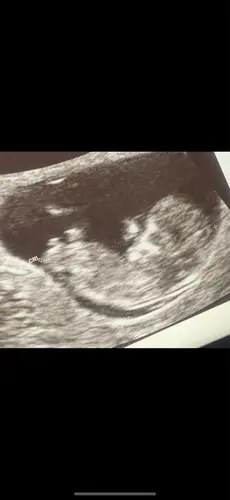

Pas 11 weken, maar de verloskundige dacht al wel een meisje te zien, maar zei erbij dat we er nog niet vanuit kunnen gaan (al had ze het de laatste tijd wel steeds goed bij anderen). Ik dacht zelf eigenlijk ook duidelijk een meisje te zien. Ben benieuwd :)